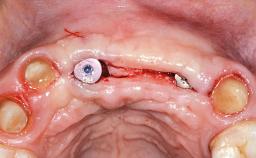

Replacement of Four Incisors with a Fixed Partial Denture on Two Narrow-Neck Implants after Implant Failure

| Bone Augmentation | Horizontal|Staged|Vertical |

| Augmentation Materials | Autogenous block(s)|Xenogenous|Membrane |

| Bone Volume | Deficient vertically or deficient vertically AND horizontally |